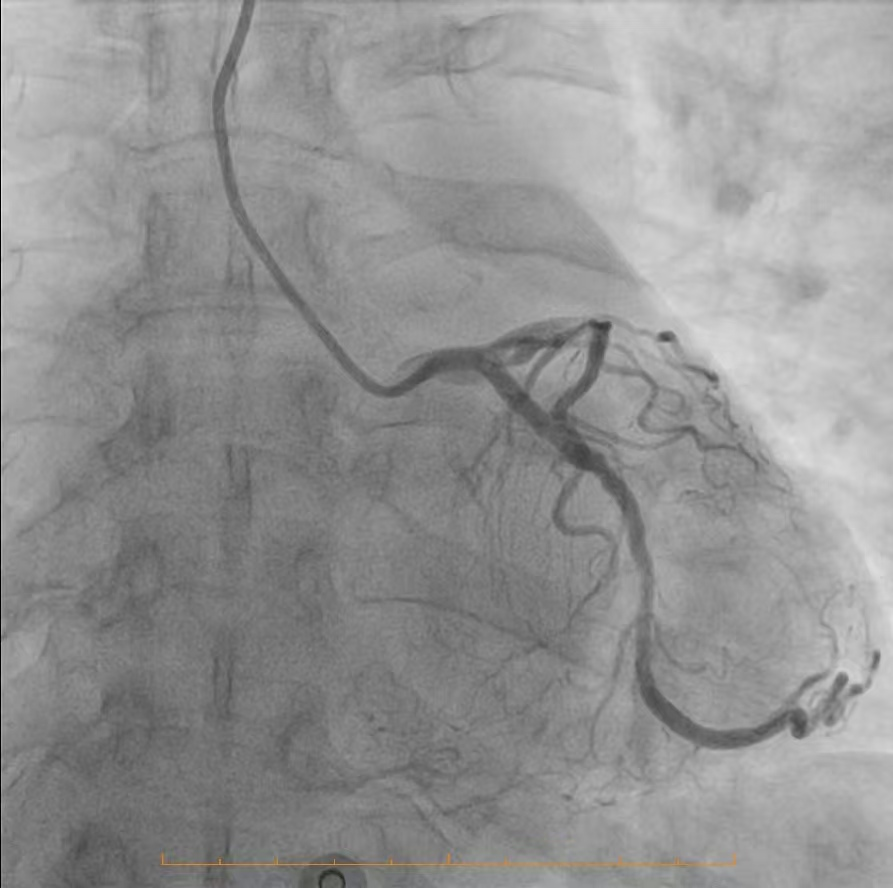

精准研判,明晰战场:冠脉造影揭示严峻挑战

为了制定万无一失的手术方案,必须首先精准“侦察”敌情。团队为患者进行了冠状动脉造影检查,结果清晰地揭示了心脏血管内严峻的形势:造影显示,患者冠脉分布呈右优势型。左主干未见明显异常,这为手术提供了一个相对安全的基础。然而,危机四伏:前降支——心脏最重要的供血血管之一,其近段开口处及以下部位存在约80%的严重狭窄,而中段更是出现了高达90%的极重度狭窄,血流已岌岌可危,是引发严重心绞痛甚至心肌梗死的主要“罪犯血管”。回旋支近段亦存在约60%的狭窄,影响了侧壁的血液供应。情况最为凶险的是右冠脉,其近段有50%的狭窄,而中段以下已经完全闭塞,远段仅能依靠来自左冠脉系统的微弱逆灌注血流勉强维持,这解释了患者为何症状如此严重,生命时刻受到威胁。

冠脉造影影像1